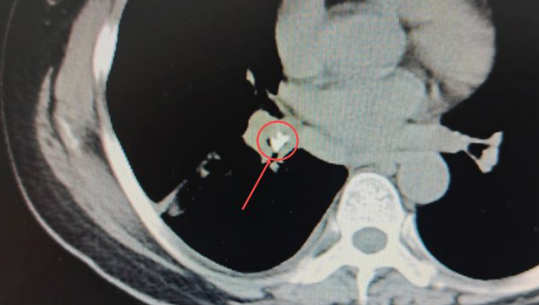

在CT影像中能夠很清晰地發(fā)現(xiàn):患者右肺葉已經(jīng)出現(xiàn)大面積實(shí)變[1],形成“白肺”(正常的肺葉組織在CT影像中呈黑色),在右肺基底段的一截支氣管中,有一個類似鈣化的“亮點(diǎn)”。醫(yī)生們進(jìn)一步仔細(xì)查看,發(fā)現(xiàn)這個亮度極高的異物顯示出的密度與骨骼的密度相近。

安女士肺部CT影像中極不尋常的“亮點(diǎn)”,馬上成為醫(yī)生們高度關(guān)注的疑點(diǎn),這也進(jìn)一步印證了礦總呼吸科專家做出的推斷:果然有異常的東西滯留肺內(nèi),才導(dǎo)致患者如此嚴(yán)重的咳喘癥狀。

▼紅圈內(nèi)即卡在肺內(nèi)的異物

孟醫(yī)生說:“病人原本的右肺有三葉,從CT中能明顯看出其中一葉完全實(shí)變,張不開。如此大面積的肺實(shí)變?nèi)绻荒芗皶r疏通,很可能導(dǎo)致后期肺器官的萎縮,整個肺下葉都會跟著喪失呼吸功能的?!?/p>